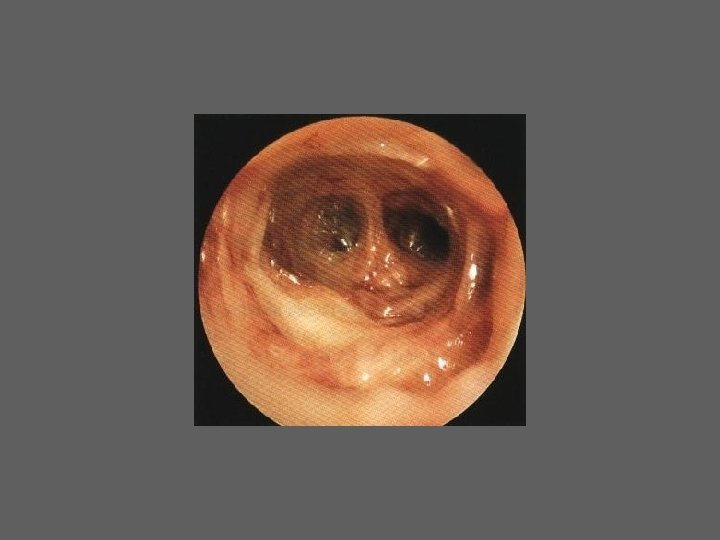

HISTEROSCOPIA - INDICAÇÕES Todas a situações em que se julgue vantajosa uma visualização completa da cavidade uterina, em particular: – Metrorragias – Dismenorreia adquirida – Infertilidade – Abortamentos de repetição e parto pré-termo – HSG anormal – DIU “perdido” – GIFT e ZIFT – Tratamento cirúrgico da patologia intracavitária: ● pólipos, miomas, septos, sinéquias, recessões endometriais ● baixos custos, reduzida morbilidade

HISTEROSCOPIA - MATERIAL CO 2 – Insuflador – Metrorragias max. 100 ml /min p < 100 mm Hg liquido (soro glicosado, dextrano, etc. ) – Fonte de luz fria – Histeroscópio (3, 5, 7 mm) – rígido ou flexível – Bainha e instrumentos cirúrgicos (pinça de biopsia, tesoura, etc.